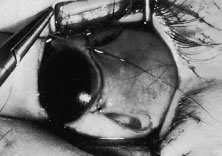

A no. 15 surgical knife or other similar instrument is used to penetrate the conjunctiva at the limbus (Fig. 50). Care is taken to approach the limbustangential to the globe so that inadvertent penetration of the sclera or cornea is avoided. A Westcott scissors also may be used to incise the conjunctiva at the limbus. To facilitate this step, conjunctiva is lifted gently with a 0.5-mm Castroviejo forceps (see Fig. 50).

|

A blunt-tipped Westcott scissors is used to extend the incision for about 3 clock hours (Fig. 51). Once the fused area of conjunctiva and anterior Tenon's capsule has been penetrated, blunt dissection is performed to carry the limbal incision back toward the muscle. This maneuver is best accomplished by directing the closed tips of a blunt-tipped Westcott scissors into the tissue and letting them open to spread the tissue in a plane between the scleral surface and the underside of Tenon's tissue. The limbal incision is extended radially with a Westcott scissors (Fig. 52). Care is taken to avoid cutting into the anterior portion of the rectus muscle insertion (Fig. 53).

|

|

Figure 54 shows the conjunctiva being elevated by the assistant with Castroviejo forceps. The anterior extension of the muscle can be seen.